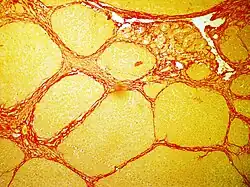

In bright field microscopy the following can be observed:

• The nuclei in yellow

• The cytoplasm in yellow

• Collagen fibers in red

• Muscular fibers in yellow

• Red blood cells in yellow

Sirius red staining in rat liver, where the red color indicates collagen deposition[3]